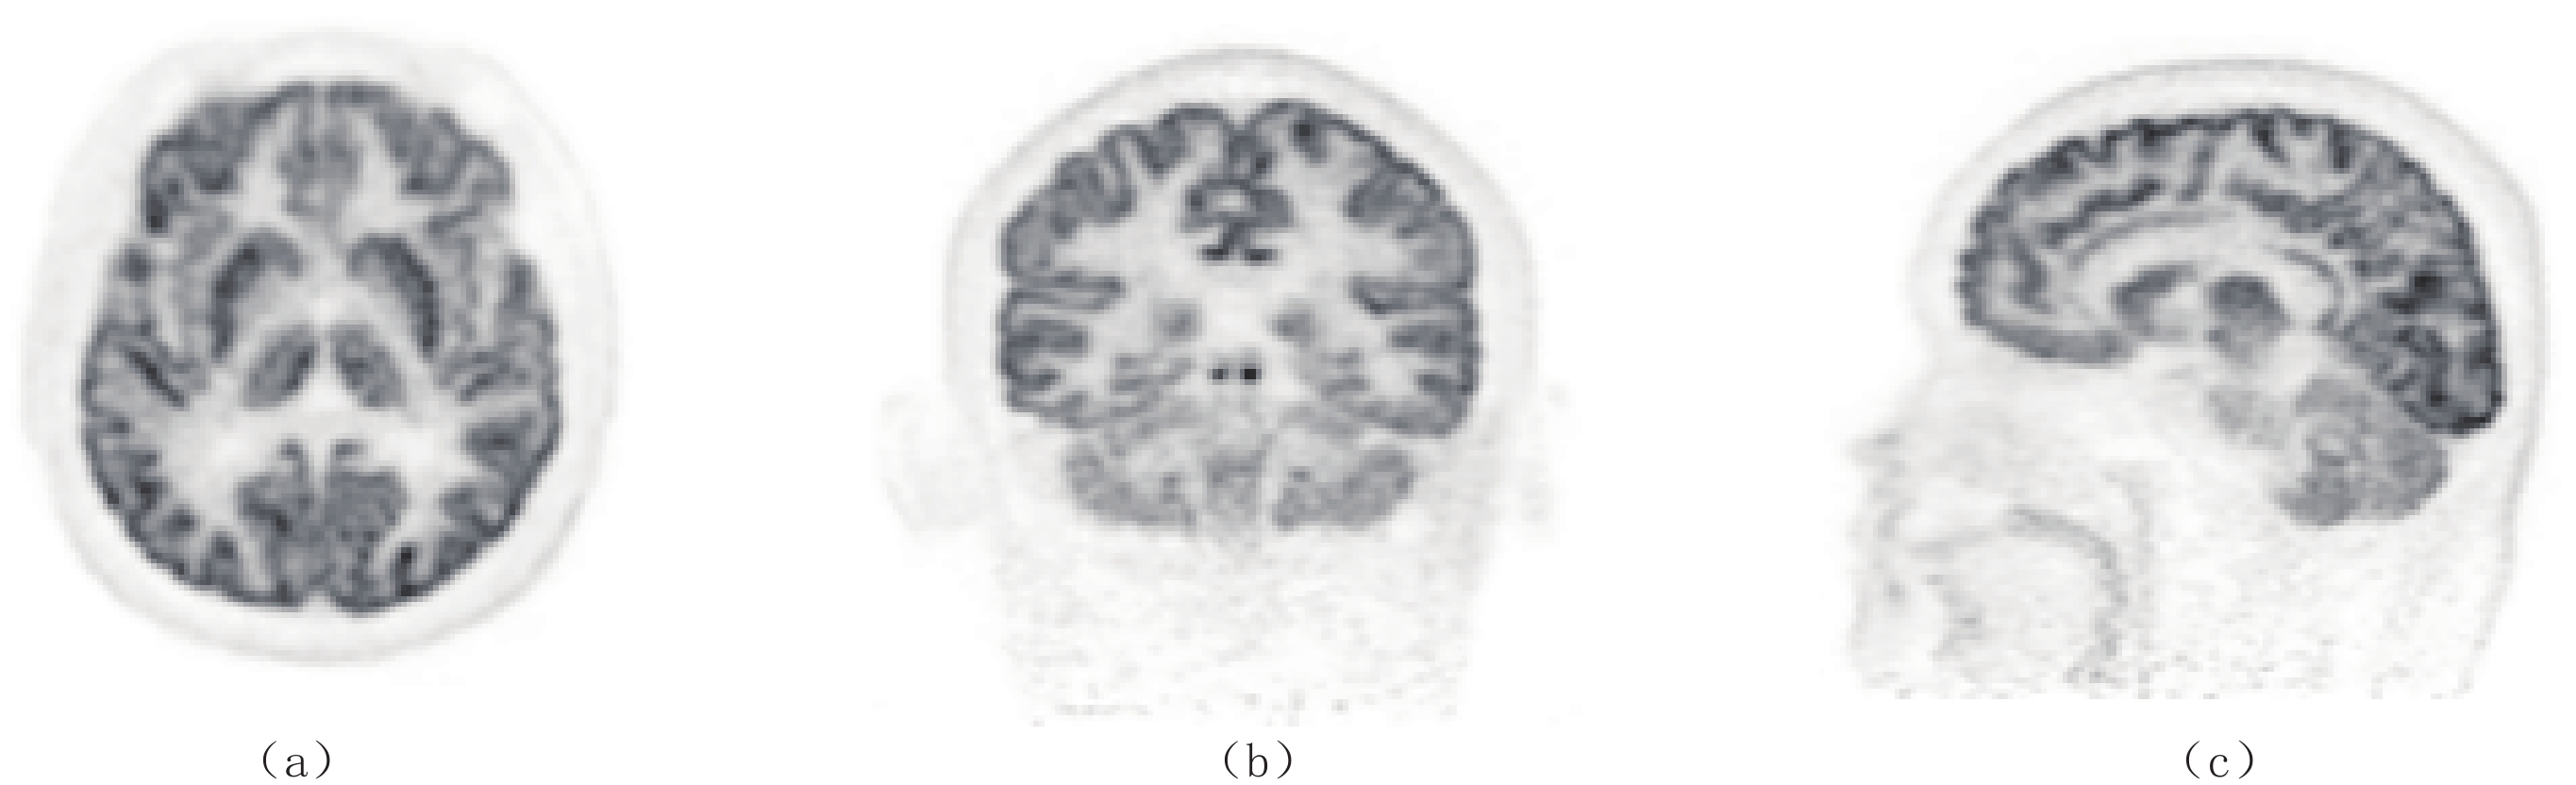

首个面向脑部专用的全数字PET产品DigitMI i30也迅速获得NMPA批准,成为第6款进入市场的全数字PET医疗器械,也是国内仅有的脑部专用PET医疗器械(图3)。由于全数字PET技术架构的灵活性,脑部专用全数字PET原理样机仅用3个月即完成研制[17],并用两个月完成384例科研临床试验[18],开展包括脑胶质瘤、帕金森、阿尔兹海默等8种脑疾病的临床诊断,取得了相对临床全数字PET/CT具有显著空间分辨率优势的图像[19](图4)。i30系统在原理样机上进一步优化,继续采用单PET设计,通过人工智能的训练,无需CT系统,仅使用PET数据即能完成自衰减校正,在性能上展现了极大潜力,是全球首个优于250 ps时间分辨率的脑部PET系统,并具备超过20 kcps/MBq的超高灵敏度。